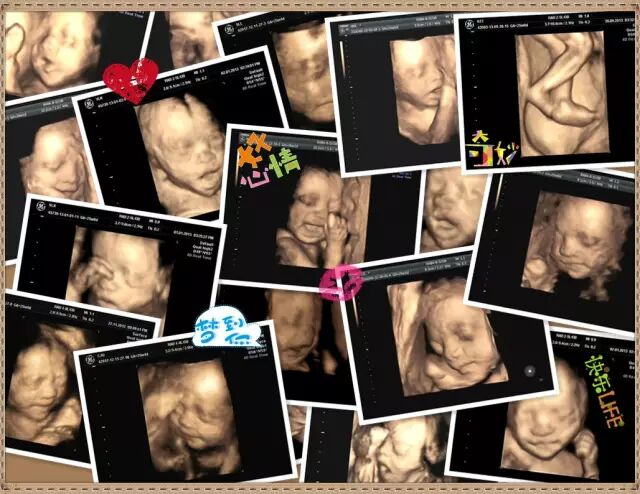

亲爱的爸爸妈妈们,你们还记得第一次看到立体的宝宝模样时的心情吗?难以想象,那张小小的四维彩超图片上出现的小家伙,会是自己此生最难以放下的牵挂。

四维彩超还能清晰显示胎儿在宫内的动态,让准爸妈一起观看宝宝在宫内各种动作神态,体会生命最初的感动。让宝宝拥有独一无二的0岁相册,留下永久的记忆。